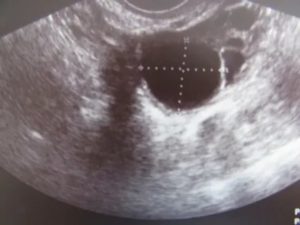

УЗИ показывает желтое тело в виде неоднородного образования. Обычно оно появляется на одном из яичников – правом или левом. Это говорит о том, что с определенной стороны был образован доминантный фолликул. При этом неважно, на каком из яичников появилась железа – развитие беременности будет проходить одинаково в обоих случаях.

На УЗИ желтое тело определяется как округлое неоднородное образование.

Его видно и при методике исследования через брюшную стенку (трансабдоминальная методика УЗИ), но более достоверные результаты диагностики получают при трансвагинальном методе с использованием внутривагинального датчика.